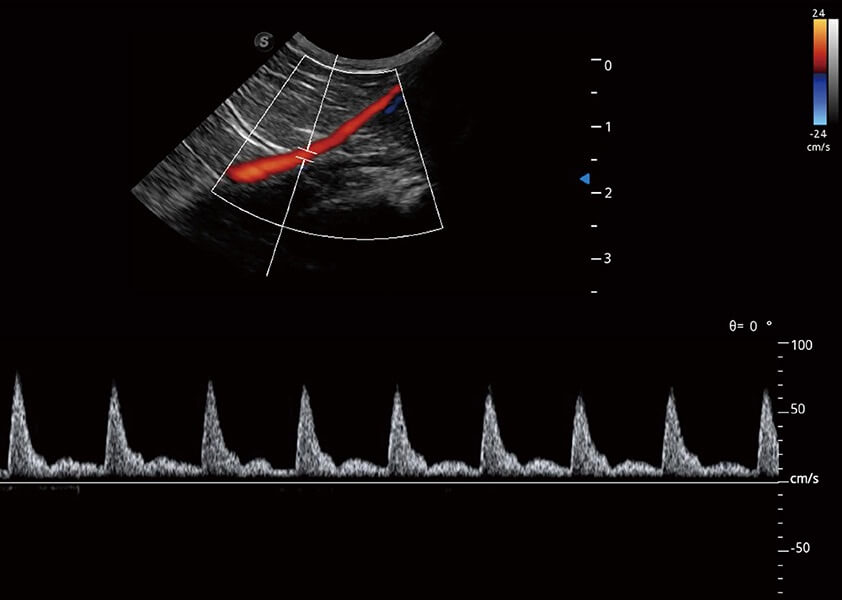

ProPet 60 作为一款高端台式动物超声设备,为动物医生的日常诊断提供了一系列贴合动物临床需求、解决临床实际问题的高级成像功能。凭借全系列高清探头,满足医生对腹部、心脏、生殖、浅表、肌骨等成像的所有需求,切实帮助您提升检查效率,提高诊断信心。

动物是人类最亲密的朋友和最值得信赖的伙伴。玖鼎集团也一直致力于探索动物专用的超声影像解决方案。 全新推出的ProPet系列,是玖鼎集团在动物超声影像智能化、专业化、精准化的一次跨越式革新。动物不能用言语来表述自己的不适,通过超声影像,ProPet系列搭建了动物医生与不同物种沟通的“桥梁”,为动物医生注入了“治愈之力”。